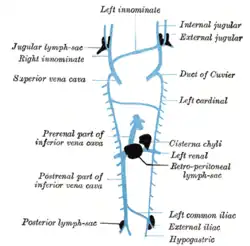

Scheme showing relative positions of primary lymph sacs.

Scheme showing relative positions of primary lymph sacs. -